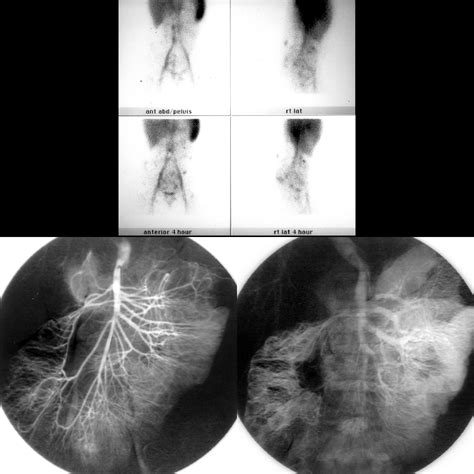

The diagnosis of a Blue Bleb Nevus is typically made through a clinical examination. A dermatologist will visually inspect the nevus and may use a dermatoscope to examine it more closely. A dermatoscope is a handheld device that magnifies the skin and allows the doctor to see the structure of the nevus in detail.

In some cases, a biopsy may be performed to confirm the diagnosis. A biopsy involves removing a small sample of the nevus for microscopic examination. This procedure is usually done under local anesthesia and is generally safe and well-tolerated.